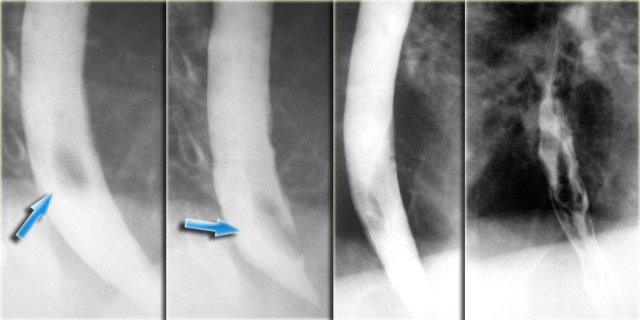

Tortuous aorta

A tortous descending aorta is a common cause of extrinsic impression on the esophagus.

The image on the far left shows a narrowed distal esophagus.

Oblique view shows esophageal indentation by aorta with obtuse margins (arrows) characteristic of extrinsic compression.

On the far left the normal aortic arch impression on the esophagus.

This impression can be enlarged if there is dilatation of the aorta as seen in this patient with a mycotic aortic arch aneurysm (arrows).

On the left 3 images of a patient with a coarctation.

On the chest film the 'Figure 3' shape of aortic knob due pre and post stenotic dilatation (arrows).

The barium study demonstrates the 'Reverse 3 figure' indention of esophagus by pre and post stenotic aortic dilatation (arrows).

An angiogram demonstrates a coarctation with pre and post stenotic dilatation in another patient.